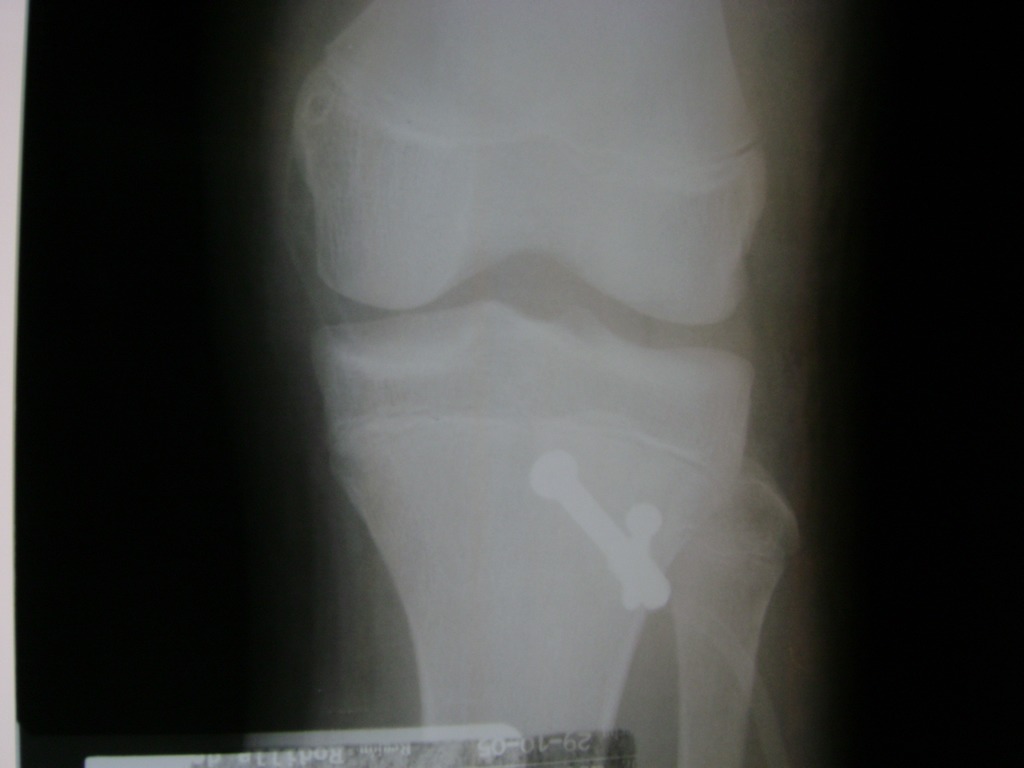

Cirugía de Fémur - Rodilla

La artroscopia de rodilla es un cirugía en el cual la estructura interna de la articulación es examinada ya sea para realizar un diagnostico o para realizar un tratamiento, este procedimiento se realiza utilizando un instrumento parecido a un pequeño tubo llamado artroscopio.